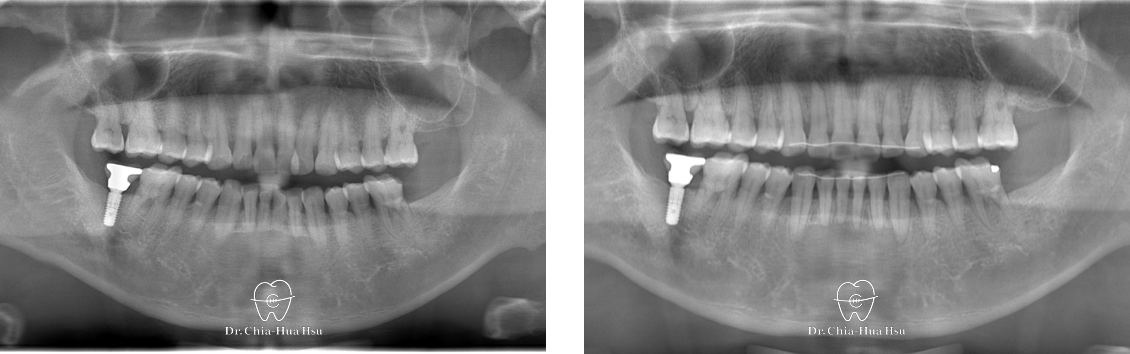

第一套隱適美牙套(40副)

第二套 追加牙套 additional aligner(18副)

治療前

治療後

治療前

治療後